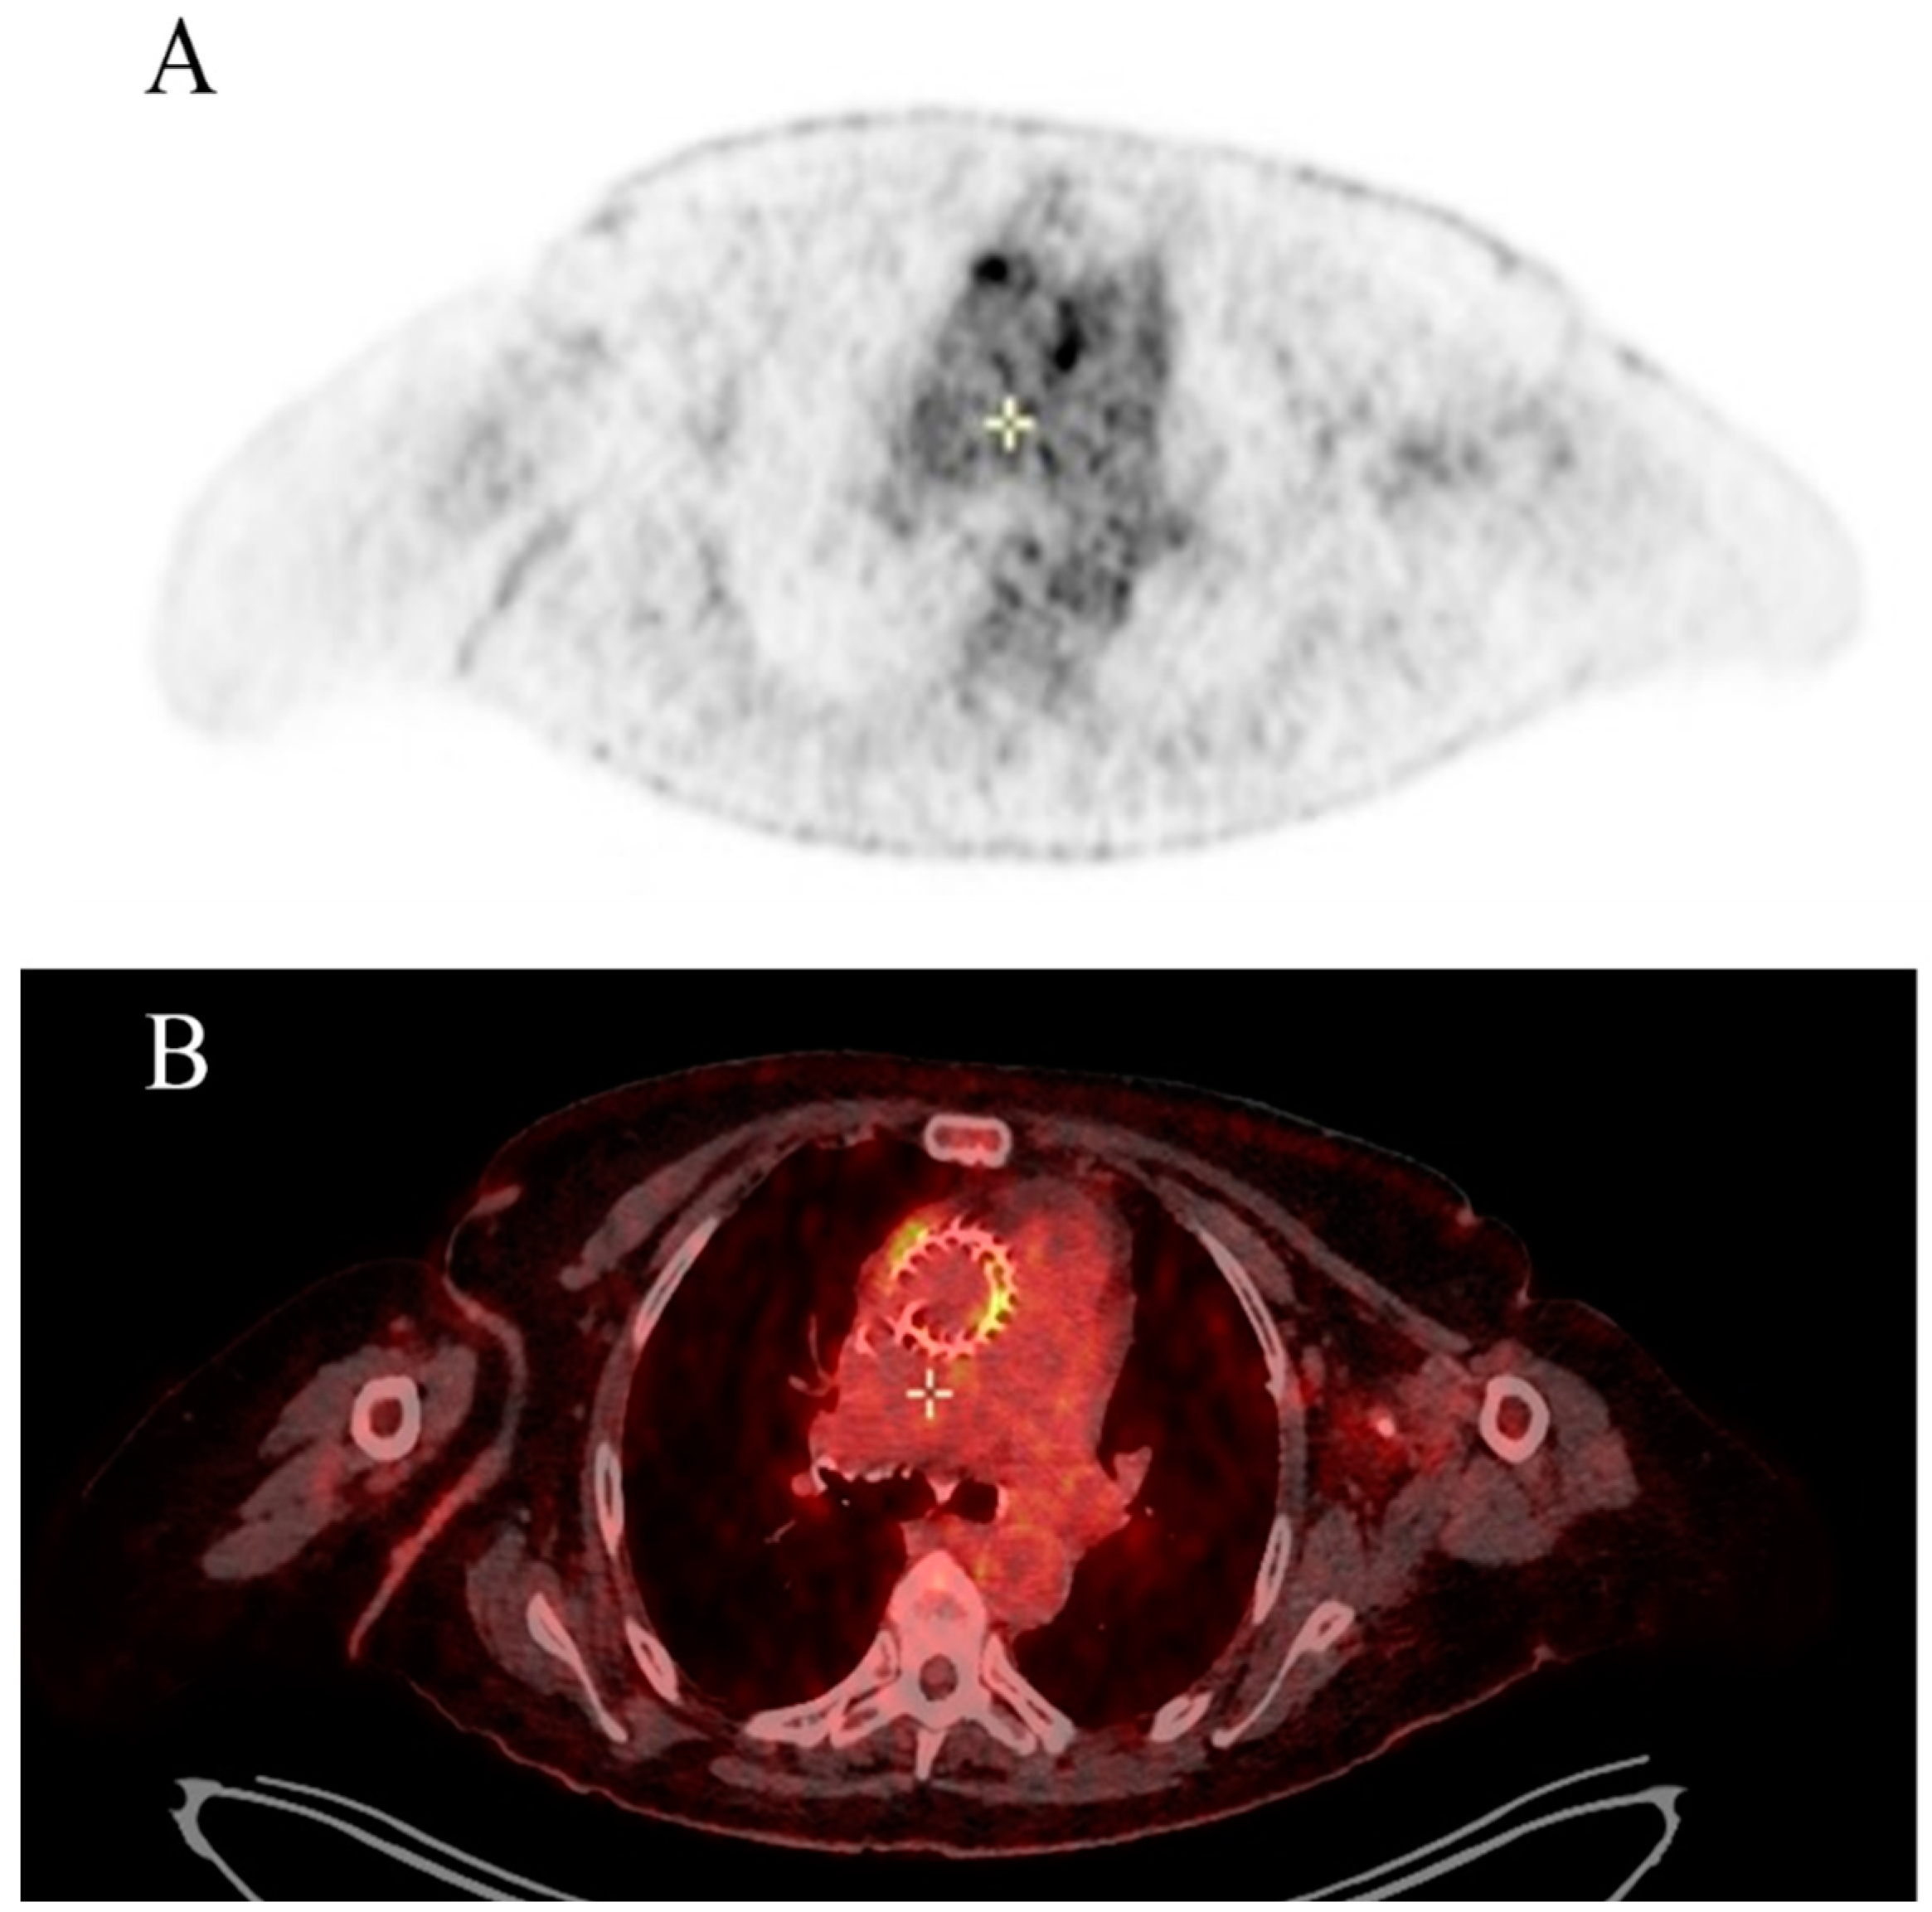

During hospitalization, transthoracic echocardiogram (TTE) was negative for vegetations and para-valvular leak; however, the presence of TAVI leaflet thickening and augmented transvalvular gradient were observed. Brain computed tomography (CT) scan showed two recent ischemic lesions which evoked a possible embolic aetiology. Transoesophageal echocardiogram (TEE) showed a mobile vegetation attached to the frame of the transcatheter prosthetic valve and an abscess in the intervalvular fibrosa. Positive blood cultures for Enterococcus faecalis completed the diagnosis of IE. A Fluorodeoxyglucose positron emission tomography/computed tomography (FDG-PET/CT) also confirmed multifocal uptake of the prosthetic. Figure 1 The patient is referred to a cardiac surgeon for consideration of aortic-valve replacement. Figure 2